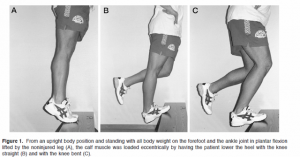

Recovery/Rehab Phase 1: The second phase can be started based upon your symptoms. If pain and swelling are reduced, and you are able to accomplish low-level function without an increase in symptoms, then the acute phase is done. Keep in mind that just because you have started phase 1 of rehab doesn’t mean that you stop acute phase treatments. You need to continue to use those tools to combat flare ups. The key to phase 1 of rehab is the addition of open Kenetic chain exercises in eccentric fashion to isolate and load the involved tendon, but exercise must be pain free.  Open Kenetic chain means that your feet and or hands are not attached to a solid non-moveable surface such as the floor. Eccentric means the negative part of the lift/ exercise lowering against gravity. These exercises allow isolation of the injured tendon/muscle, control the resistance applied, and focus it to the tendon itself. With this, we can build strength and endurance over the next two weeks (or as long as it takes to resume low-level activity without pain) by slowly adding resistance (weights) along with repetitions. The last thing I introduce is low-level stretching, along with all major muscle groups starting at 30 sec holds (no bouncing) repeating 2-3x and 2 time per day. The goal is to increase the intensity of the stretch each day, as long as only the stretch is felt and not pain. When the stretches and low-level activity are successful, you have graduated to phase 2 return-to-sport level. Remember, during phase 1 you may need to exercise the “other” muscles of your body so that it stays in good physical condition.

Open Kenetic chain means that your feet and or hands are not attached to a solid non-moveable surface such as the floor. Eccentric means the negative part of the lift/ exercise lowering against gravity. These exercises allow isolation of the injured tendon/muscle, control the resistance applied, and focus it to the tendon itself. With this, we can build strength and endurance over the next two weeks (or as long as it takes to resume low-level activity without pain) by slowly adding resistance (weights) along with repetitions. The last thing I introduce is low-level stretching, along with all major muscle groups starting at 30 sec holds (no bouncing) repeating 2-3x and 2 time per day. The goal is to increase the intensity of the stretch each day, as long as only the stretch is felt and not pain. When the stretches and low-level activity are successful, you have graduated to phase 2 return-to-sport level. Remember, during phase 1 you may need to exercise the “other” muscles of your body so that it stays in good physical condition.

Phase 2/Return-to-sport: Characterized by the continuation of the above, while adding close chain exercises and one plane drills at 50% of game intensity. Close chain exercises are those where your feet or hands are on a solid surface. Examples of this are Lunges, squats, pushups. These types of exercises are functional in that they create multi-planar contractions at many different joint levels along with many different types of muscle involvement and speed. For example, an athlete with patellar tendonitis who has been doing low load, high repetition leg extensions in Phase one, is now pain free and wants to return to soccer might start phase 2 with 4 inch quick steps (close chain and one plane) for 20-30 seconds x 3 reps at 50 percent, line hops with same parameters working front to back, side to side and diagonals. Balance/ proprioception exercises should also be introduced at this time to focus on the patient’s ability to hold joint posture, muscle co-contraction and know where his/her body is in space. When the athlete is able to perform these, along with other harder exercises at a 100%, its time to start a gradual return to sport at 50-75% of his/ her ability.